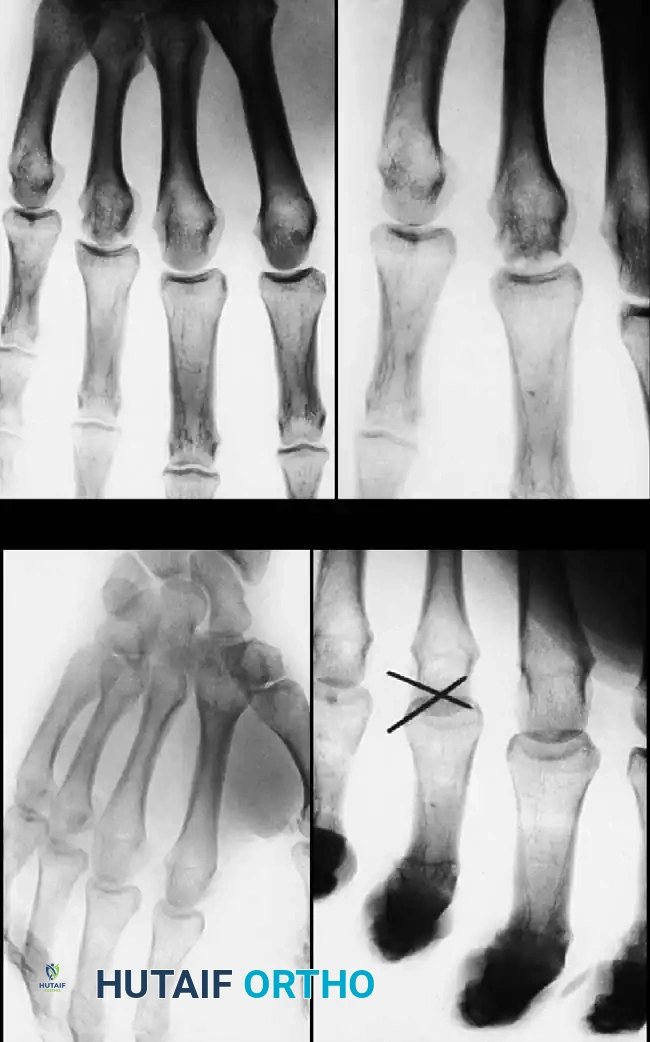

2. Interfragmentary Screw Fixation

Long oblique or spiral fractures of the metacarpal shaft (where the fracture length is at least twice the diameter of the diaphysis) are ideally suited for interfragmentary lag screw fixation.

This technique provides absolute stability, allowing for immediate postoperative mobilization. It requires minimal periosteal stripping and avoids the hardware prominence associated with dorsal plating. Typically, two or three 1.5 mm or 2.0 mm cortical screws are utilized, placed perpendicular to the fracture plane to maximize compression.